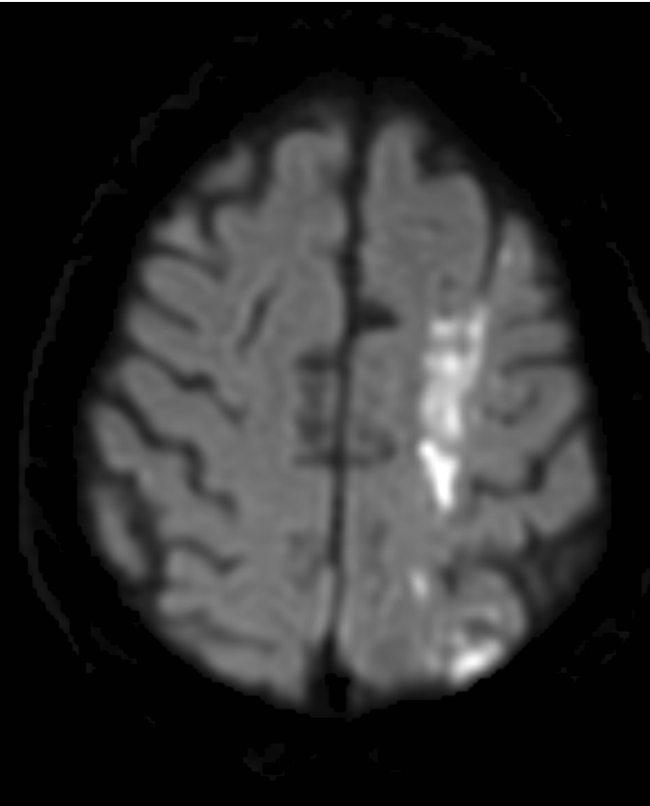

Border zone infarcts often tell a story. Unilateral cerebrum? Think proximal stenosis. Bilateral cerebrum & cerebellum? Think systemic event. In this case, nasopharyngeal ca → ICA occlusion → symptomatic border zone infarcts. See http://bit.ly/2Sdu5xa to learn more!pic.twitter.com/7fYYg8aReq